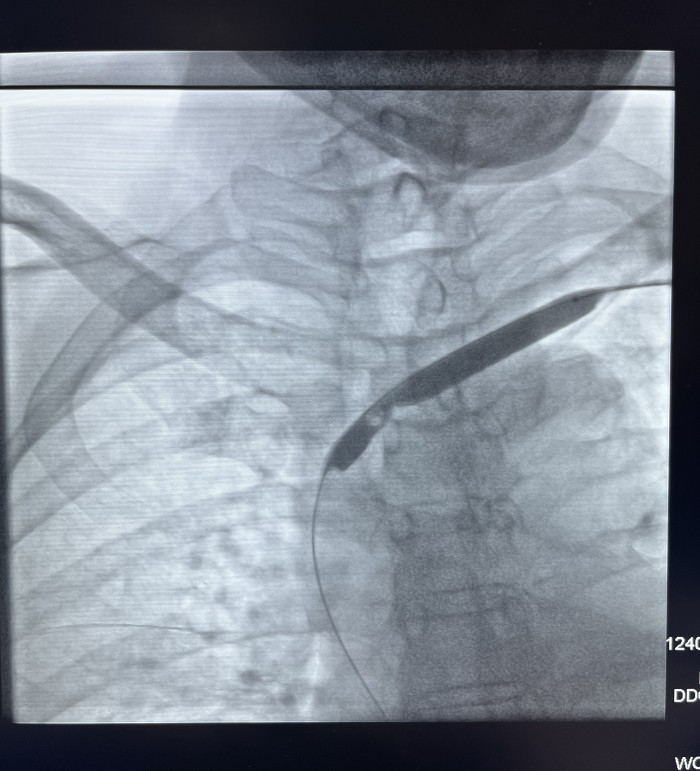

患者赵某,因两侧多囊肾致肾功能衰竭在我院行血液透析三年半。近一年来患者出现血透后左上肢肿胀并伴头面颈部表浅静脉怒张,近三月透析时人工内漏内血流量下降。经我院介入血管科副主任芮兵门诊详细询问病史及查体后收治该患者入院,行左上肢CTV及左上肢静脉造影检查显示:左头臂静脉起始部重度狭窄。在芮兵副主任医疗团队精心制定手术方案,排除手术禁忌后,成功实施了经皮左头臂静脉球囊扩张成形术,术后患者左上肢肿胀明显消退,透析时血流量>200ml/min,可以完成透析。